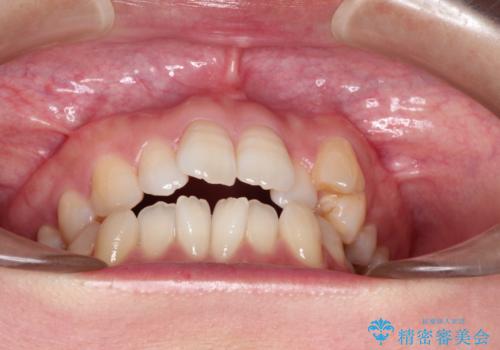

- 前歯がガタガタなのと、前歯でものが噛めないことを主訴に来院されました。

前歯の叢生があり、上下の前歯が接触していない開咬という状態でした。

左側の上下の前から4番目の歯を抜歯して、矯正することとしました。

ガタガタがなくなり、上下の前歯が接触すようになり、見た目とともに咬みやすくすることができました。